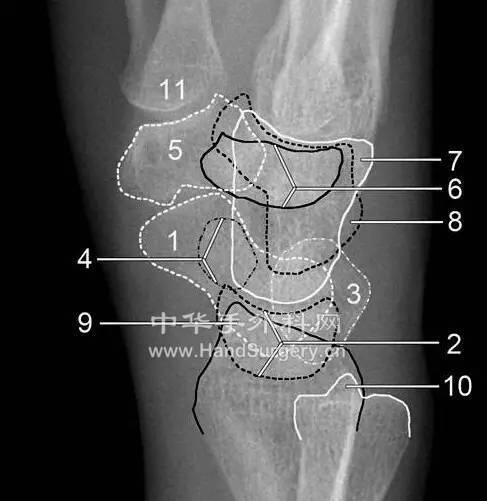

腕关节Gilula线

楼主| 发表于 2020-5-10 23:48:59 | 显示全部楼层

侧位